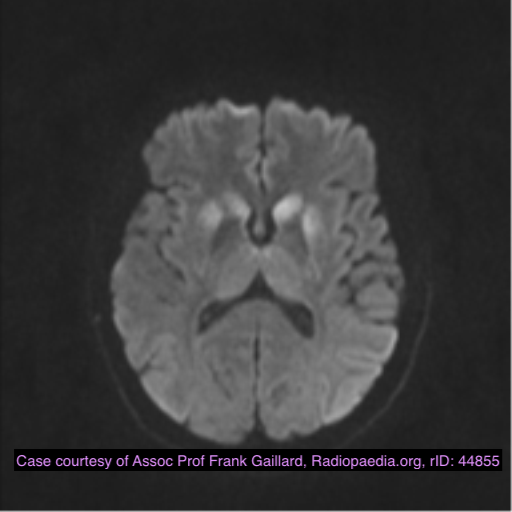

CNS capillary telangiectasia

Dr Daniel J Bell◉ and Dr Yuranga Weerakkody◉ et al.

CNS capillary telangiectasiae(s) are small, asymptomatic low flow vascular lesions of the brain.

Radiographic features

Capillary telangiectasias are mostly located in the brainstem (especially the pons). They are more often solitary, but sometimes can be multiple. They have only become widely recognised in the radiology community following the introduction of MRI, as they are usually not seen on CT and DSA 2-5.

MRI

They appear as subtle lesions with no mass effect.

T1: typically iso to low signal compared with brain parenchyma

T2: normal or slightly increased signal intensity

FLAIR: normal or slightly increased signal intensity

T2*: low signal intensity

thought to be due to deoxyhaemoglobin from sluggish flow, not haemorrhage 2

T1 C+:

may demonstrate stippled enhancement

if large, can show branching/linear draining veins